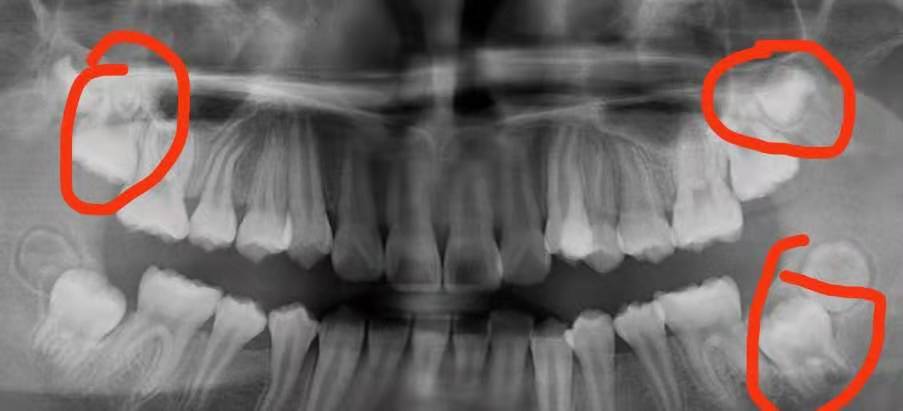

①智慧齒威脅鄰牙:當智慧齒威脅到鄰牙的時候,智慧齒阻生或者生長空間有限,此時應該考慮拔除智慧齒。否則長此以往,鄰牙可能被擠歪頂壞,出現一系列後遺症。因此此時智慧齒應該考慮拔除。

③智慧齒導致食物填塞:如果智慧齒導致鄰牙食物填塞,極其容易導致鄰牙側面蛀牙,並且蛀牙情況難於杜絕,此時考慮拔除。

④智慧齒埋伏生長:當智慧齒完全不能生長出來,此時可以考慮拔除。